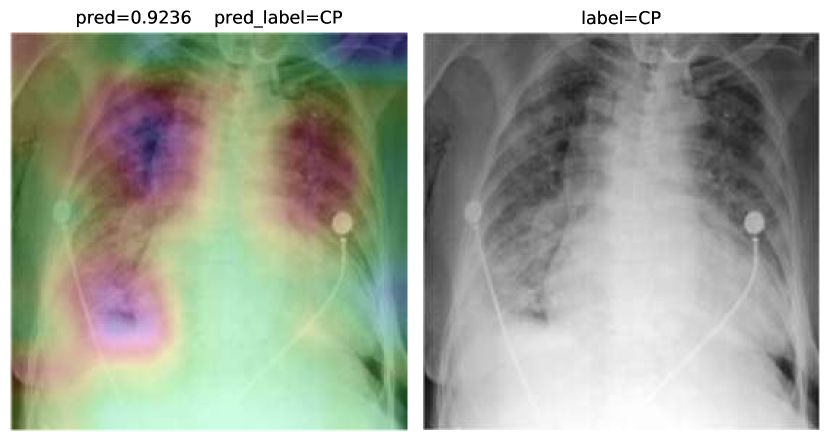

Accuracy score is 81.04%, with f-scores of 0.85 and 0.76 for CP and CAP classes, respectively. In a number of cases, especially in the first stages of virus progression, CP has unilateral findings. Also, CAP may cause bilateral consolidations. Therefore, some cases are expected to be misclassified between CP and CAP. From the confusion matrix, it could be seen that a relatively high number of images are misclassified between CAP and normal. A potential reason for this issue is considered to be related to wrong labeling. Besides, some CAP CXRs are from patients with early-stage disease development. To confirm the model performance, Grad-CAMs are plotted in Fig. 19.

Refer to caption

Figure 19: COVID-CXNet multiclass classification visualization results

The model is properly looking at one lobe for detecting CAP and both lobes for CAP and normal images. There are some wrong labels, nevertheless. A figure containing more visualizations is found in Appendix C. To further enhance statistical scores, a hierarchical approach is implemented. In the first level, we classify images into normal and pneumonia classes. In the second level, pneumonia images are categorized into CP and CAP. Final confusion matrix is illustrated in Table 5.